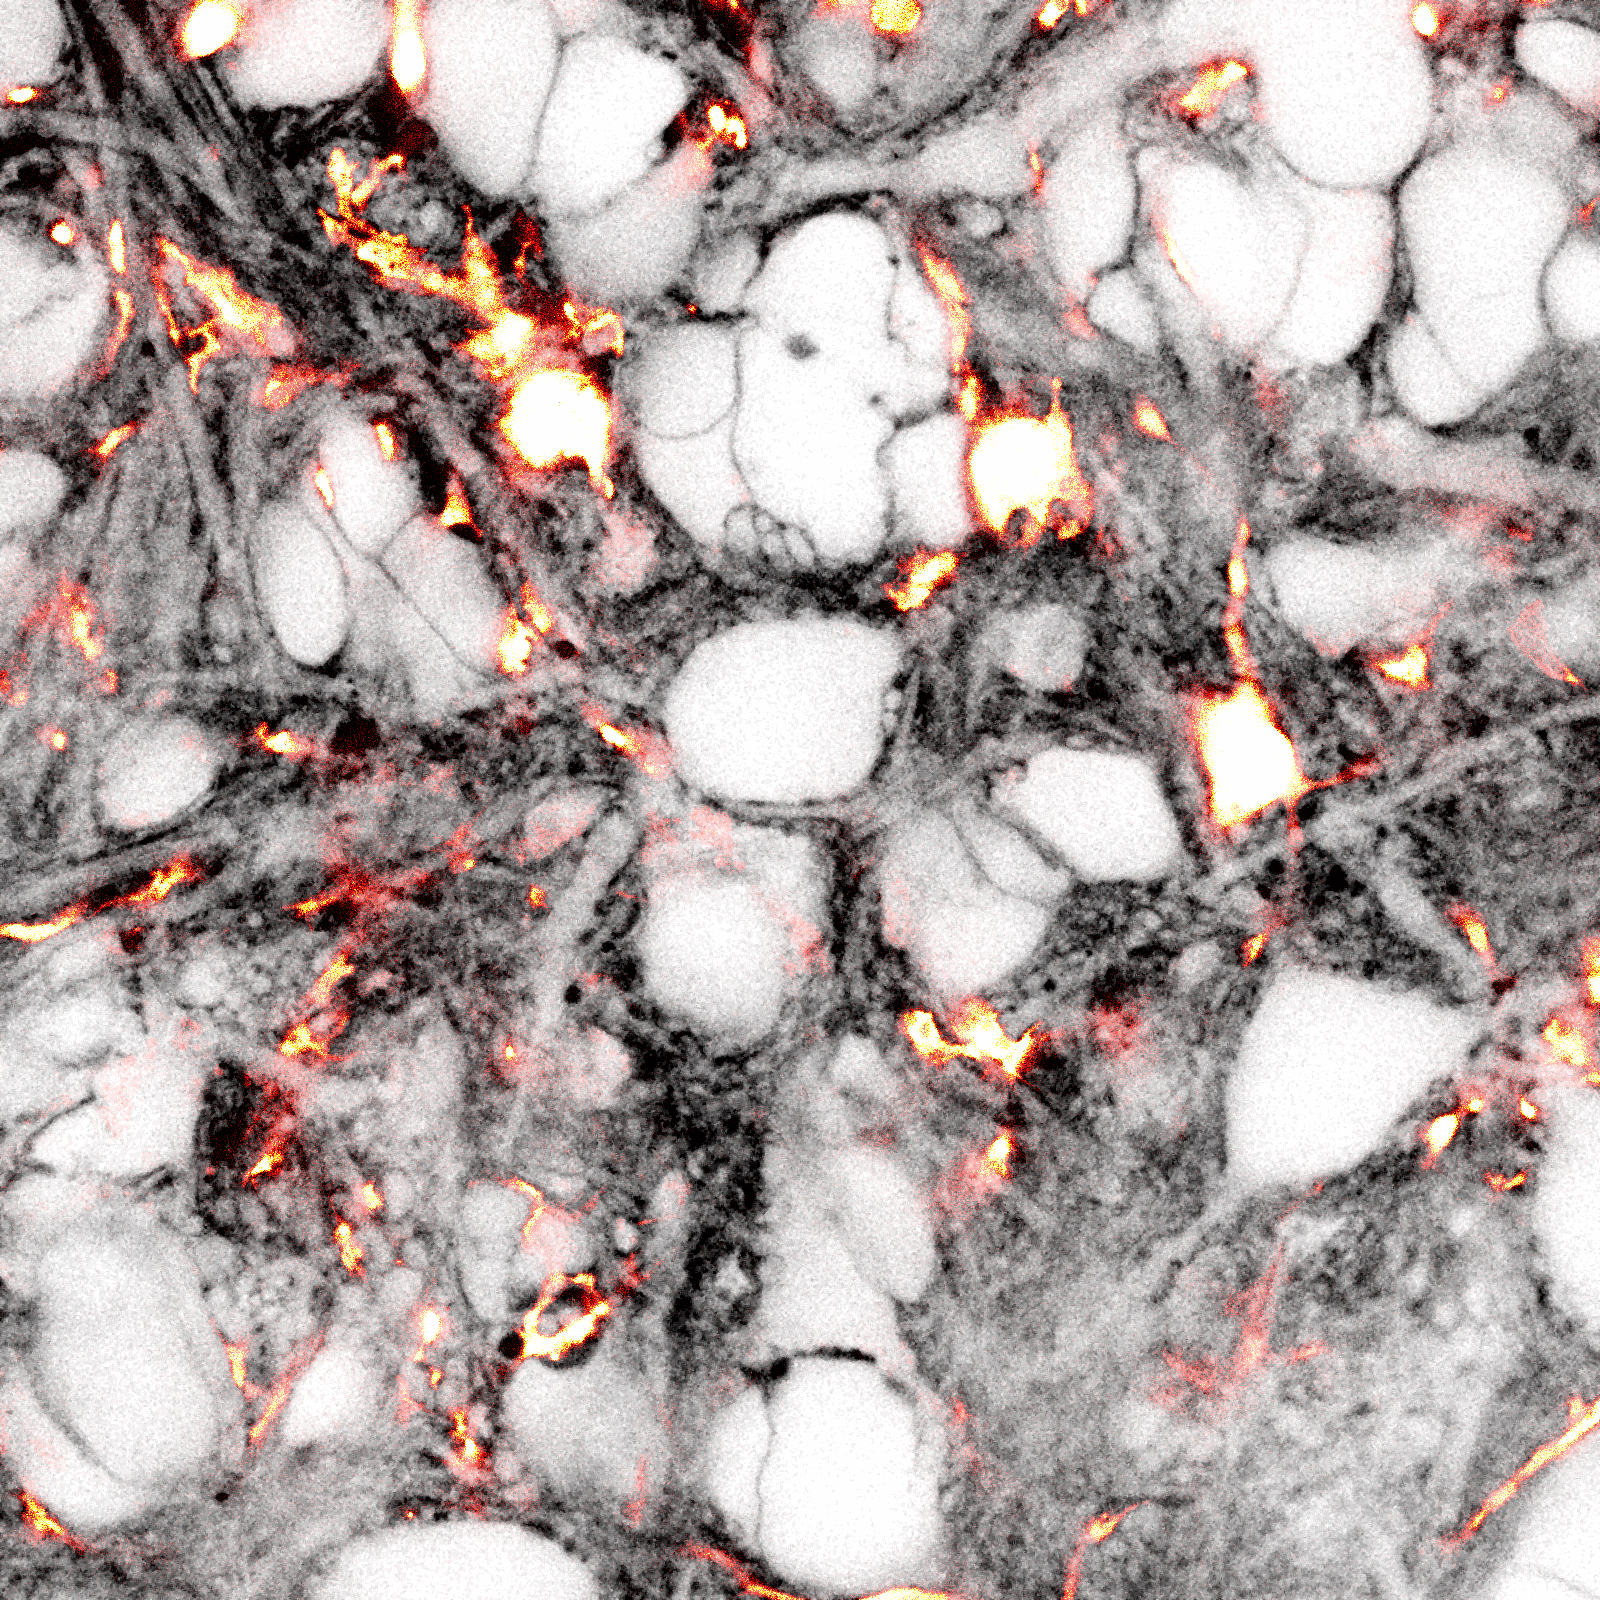

Dembitskaya Y, Boyce AKJ*, Idziak A, Pourkhalili Langeroudi A, Le Bourdellès G, Girard J, Arizono M, Ducros M, Sato-Fitoussi M, Ochoa de Amezaga O, Oizel K, Bancelin S, Mercier L, Pfeiffer T, Thompson RJ, Kim S.K., Bikfalvi A, Nägerl U.V. (2023) Shadow imaging for panoptical visualization of living brain tissue. Nature Communications.

*co-first author